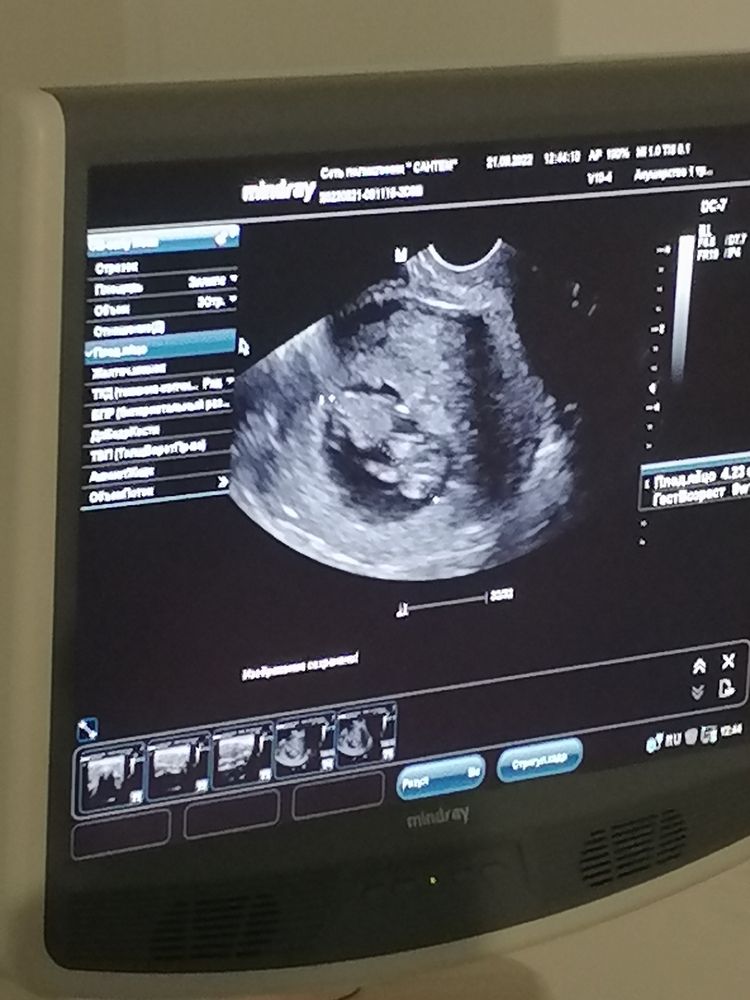

Врач пустил нас вместе, делали и вагинальное и через живот, все посмотрели. Нам малыш показал представление. Так шивелился, что не могли посчитать ктр 😂 у мужа улыбка до ушей ☺️ потом устал от нас, отвернулся и уснул ❤️

Очень рада что сходили вместе и он теперь понимает что внутри меня происходит ☺️😂 узи делали на сроке 10+2, ктр 38. Врач поставила срок 10+5